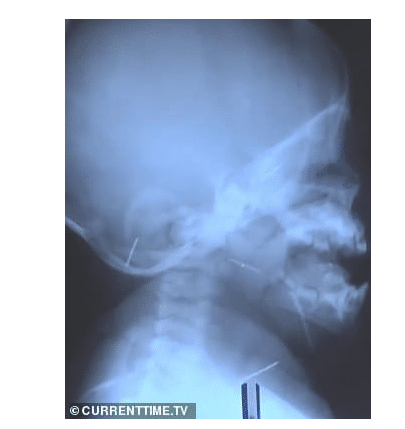

Ο μικρούλης νοσηλεύτηκε το προηγούμενο καλοκαίρι όταν ένας συγγενής ανακάλυψε μια βελόνα μέσα στο στόμα του. Το εννιά μηνών υπεβλήθη σε ακτίνες και εντοπίστηκαν 10 βελόνες. Οι γιατροί προχώρησαν σε αρκετές επεμβάσεις προκειμένου να αφαιρέσουν τα μεταλλικά αντικείμενα από το βρέφος, που έφερε βελόνες σε κρανίο, μύτη, λαιμό, στήθος και πόδια.

Όπως ανέφερε νοσοκομειακή πηγή, κάποιες από τις βελόνες είχαν σκουριάσει μέσα στο κορμάκι του όπου βρίσκονταν για περισσότερους από 3 μήνες. Αμέσως μετά το περιστατικό η μητέρα τέθηκε υπό κράτηση και παραδέχθηκε τις πράξεις της αποκαλύπτοντας και τον λόγο.